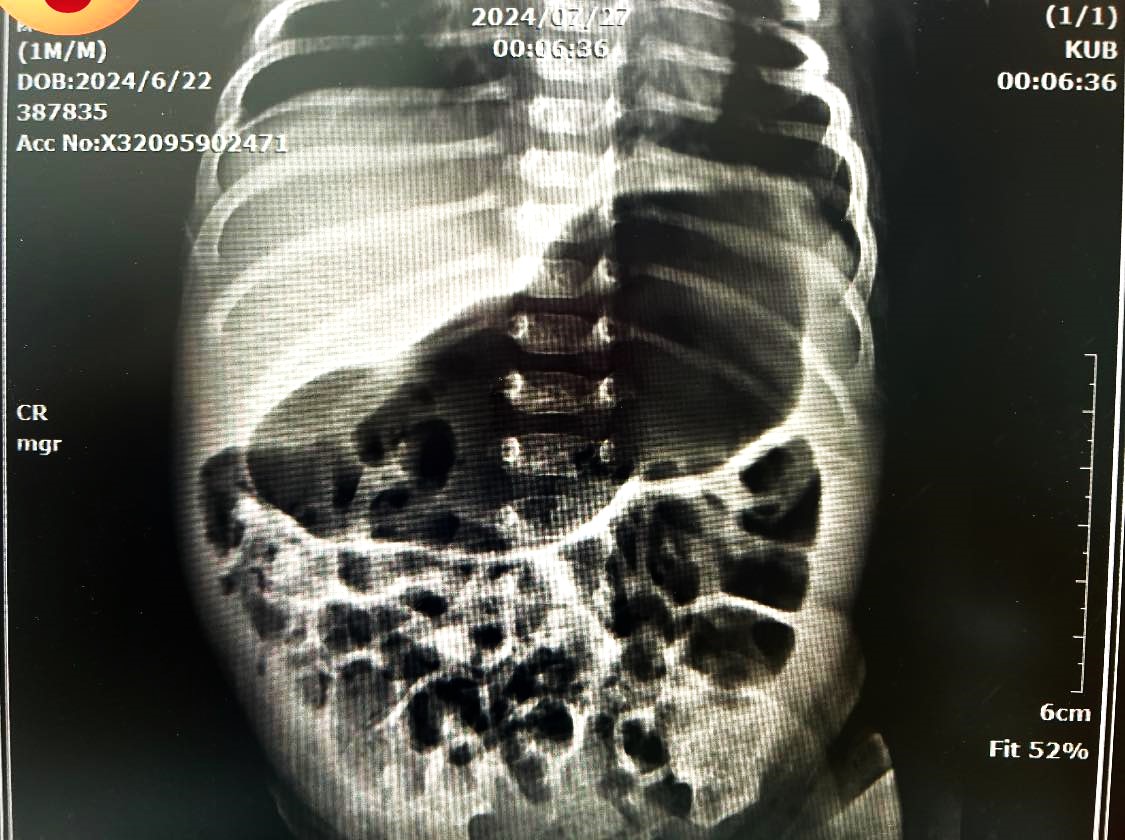

【記者黃山高高雄報導】署立旗山醫院李宗諺醫師兒童運動健康生活分享,原本喝奶正常的新生兒,約長到一個月大時,竟喝完奶就立刻噴吐出來,且吐完還想再吃但吃完又吐,情況反覆,被帶來兒科急診,李醫師覺得不太對勁,一個月大寶寶突然開始吐奶故安排腹部X光檢查發現「single bubble sign」診斷為嬰兒肥厚性幽門狹窄,須進一步住院避免脫水,尋求小兒外科醫師協助治療。

李宗諺醫師指稱,「嬰兒肥厚性幽門狹窄」顧名思義是幽門肌肉增生致通道變窄,食物無法通過幽門到達十二指腸,全部堵在胃部裡,當胃盛裝不下食物,便會從食道噴濺出來,引發嬰兒肥厚性幽門狹窄的原因未明,發生率約在千分之1.5,且男嬰的發生率是女嬰的四至六倍,尤其以第一胎男嬰機率最高。

典型的嬰兒肥厚性幽門狹窄最容易辨認的特徵,就是剛出生時喝奶情況會較順利,但在三週至三個月大之間,反而開始出現明顯嘔吐情形,幾乎餐餐餵完就出現「噴射性」嘔吐,吐出的是未消化過的無膽汁奶水,且症狀越來越嚴重。

新生兒沒有馬上出現症狀,主要是剛出生時的幽門是正常的,隨著時間越長越大,肌肉肥厚的情況加劇,才會逐漸出現症狀,目前黃金診斷的方式是超音波檢查,再透過「幽門肌肉切開術」即可徹底治療,手術時約需半小時,術後住院觀察三至四天,確認無礙就能出院。